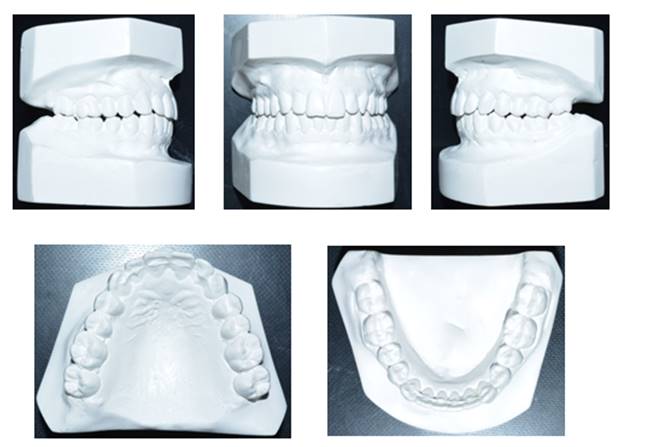

Methods: The clinical examination included extra-oral and intra-oral photographs, panoramic radiographic, lateral cephalometric, stone casts, and upper and lower arch analysis obtained from ClinCheck 3.0.The treatment planning was resolved the crowding in both upper and lower arches and the severe rotation of 33 tooth (46°) using Invisalign system as well as the canine and molar relationship, dental verticalization, adequate over jet, overbite and dental midline using the same system. The duration of the treatment was approximately eight months.

Results: In Post-treatment extra oralphotographs, no significant changes were observed at the end of the treatment. Intraoral photographs showed an important and notable improved aesthetics. The canine relationship improved slightly and molar Class Irelationship was maintained. An increase in transverse diameter was observed at the level of first premolars, second premolars and first molars. The overbite was improved. The crowding and the severe canine rotation were corrected. No obvious root resorption was radiographically evident and slight cephalometric changes.